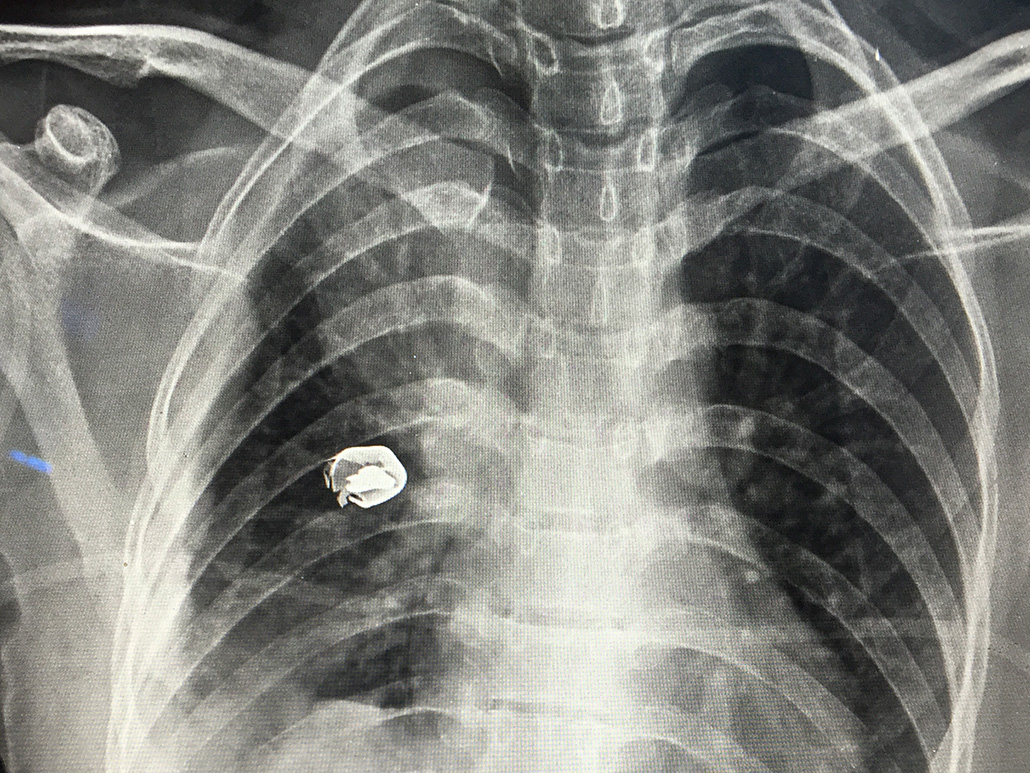

“My name is Sumaya, I am 18y and I am from Yemen. In the beginning I didn’t feel luck. I felt that it would have been better if the bullet went 5 cms towards the center of my chest. This is what war looks like: Your heart exposed to chance. But our heart is not...